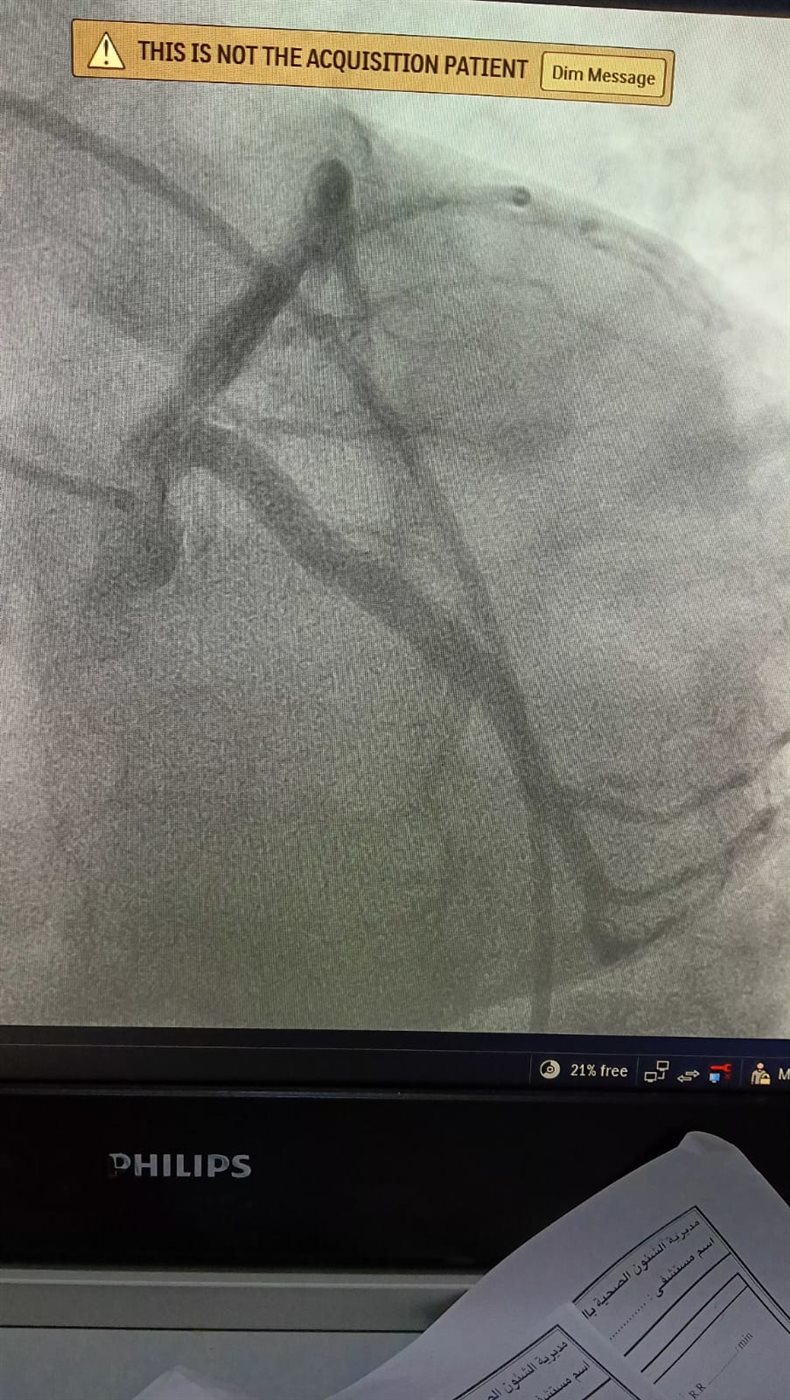

وبمجرد وصول المريضة إلى مستشفى ميت غمر العام عن طريق الإسعاف، تم إجراء الفحوصات والتحاليل اللازمة بشكل عاجل، وتجهيزها للتدخل الطبي، حيث جرى إدخالها لإجراء قسطرة قلبية تشخيصية خلال وقت قياسي، كشفت عن وجود جلطة بالشريان التاجي أثرت على تدفق الدم إلى عضلة القلب.

وعلى الفور، تم التعامل مع الحالة وإزالة الجلطة بنجاح، مما أدى إلى تحسن سريان الدم واستقرار الحالة الصحية للمريضة، وتم نقلها إلى العناية القلبية لاستكمال العلاج والمتابعة حتى خروجها بحالة جيدة.